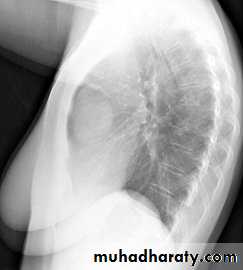

Radiographic featuresChest radiograph

It may show a superior mediastinal radio-opacity causing the deviation of trachea to opposite site. The superior margin of the radio-opacity/mass is untraceable (cervicothoracic sign).

Retro sternal goiter